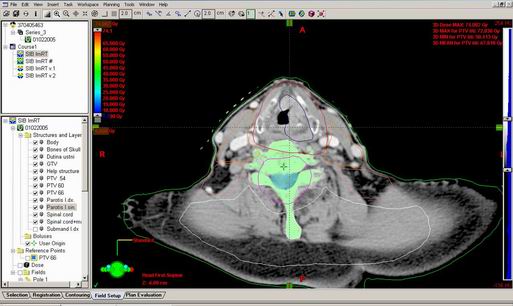

68-letý M.P.

Karcinom laryngu, T3 N2b M0, spinoca G3

Kurativní RT – SIB technika

Zakreslení struktur:

DVH:

IMRT - Kurativní RT – SIB technika

SIB IMRT for locally advanced H&N SCC: II-clinical results, Int. J.Rad.Oncol. Biolo.Phys. Vol60,No.2 pp374-387

Fyzikální dávka 66 Gy, BED 70 Gy

Dle stupně rizika postižení kolísá dávka/fr 1,8 Gy až 2,2Gy na fr.

Optimalizace v 1 plánu